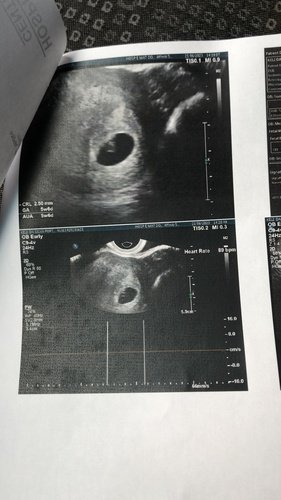

uma medicação para trambofilia. Preciso aplicar esta medicação todos os dias e o custo é muito alto. ( versa 40mg) O estado negou dar… o custo mensal é de 1950 reais 15 caixas no valor de 130,00 reais. Estou grávida de 9 semanas e tenho que tomar todos os dias uma. Quem puder ajudar agradeço imensamente 🥰 Não sou de pedir nada a ninguém mas por um filho deixamos o orgulho de lado 🤰